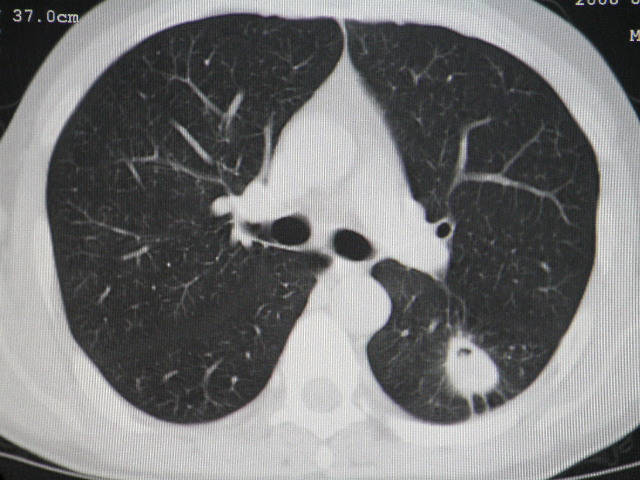

肺内结节在纵隔窗内测ct值为43hu

左肺下叶背段软组织结节,偏心空洞,周围见长纤维所条及卫星灶,首先考虑结核球,周围型肺癌待排。

左肺下叶偏心软组织肿块,边缘毛刺征,胸膜凹陷征

有肝硬化背景,肝胃间隙见不规则形,且密度不均匀的占位性病变,与肝左叶分界不清,首先考虑外生性肝癌可能性大,不排外肝胃间隙恶性占位肝脏受侵可能性。左肺下叶结节影,其内见空泡征,边缘见毛刺,从一元化的角度首先考虑转移。

1 肝脏各叶比例失调,形态失常,外缘呈波浪状。右叶萎缩,左叶 尾叶增大。2 腹腔内软组织密度肿块,低于肝实质密度,内见低密度区,并与肝脏界限欠清。腹膜后见肿大淋巴结,并与腹腔肿块关系密切。3 左肺下叶肿块,见边缘毛刺征及胸膜凹陷征,并与近肺门侧见异常血管相连。

左肺下叶偏心软组织肿块,边缘毛刺征,胸膜凹陷征,血管集束症

1肝胃韧带区域一肿块,肿块上缘与肝左叶相连。肝硬化。考虑肝外生型肝癌可能性大,不除外间质瘤。2左肺下叶背段一结节,有偏心性空洞,长毛刺,其周有多发小结节。考虑结核可能性大。